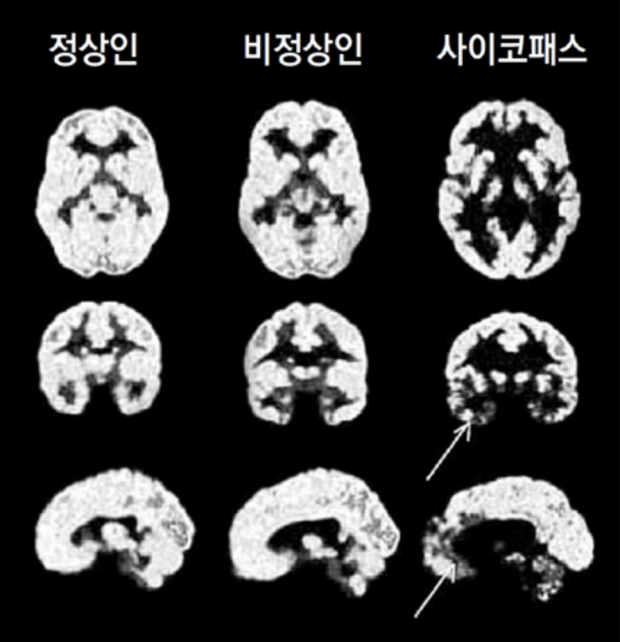

사이코패스 성향을 가진 범죄자들은 자신이 어떤 행동을 할 때, 그 행동을 하면 처벌을 받는지 안 받는지를 제대로 판단하지 못하는 것으로 나타났습니다. 세일라 호지스 몬트리온 대학 의대 교수팀은 사이코범죄자들의 재범률이 높은 이유를 맑히기 위해 사이코패스 범죄자들의 뇌를 자기 공명 영상 장치로 촬영하여 강력 범죄자, 사이코패스 범죄자, 일반일을 대상으로 각각 검사를 진행했습니다. 사이코패스 범죄자들은 사회적인 감정을 처리하는데 관여하고 있는 전문 측 전두피질과 측두극 부위가 수축돼 있는 것을 발견하였습니다. 연구팀은 사이코패스 범죄자들의 이 부분이 문제가 생기면서, 처벌을 통해 학습하지 못하는 것이라고 설명했습니다.